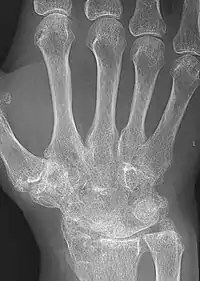

Ankylosis is a stiffness of a joint due to abnormal adhesion and rigidity of the bones of the joint, which may be the result of injury or disease. The rigidity may be complete or partial and may be due to inflammation of the tendinous or muscular structures outside the joint or of the tissues of the joint itself.[1]

When the structures outside the joint are affected, the term "false ankylosis" has been used in contradistinction to "true ankylosis", in which the disease is within the joint. When inflammation has caused the joint-ends of the bones to be fused together, the ankylosis is termed osseous or complete and is an instance of synostosis. Excision of a completely ankylotic shoulder or elbow may restore free mobility and usefulness to the limb. "Ankylosis" is also used as an anatomical term, bones being said to ankylose (or anchylose) when, from being originally distinct, they coalesce, or become so joined that no motion can take place between them.[1]